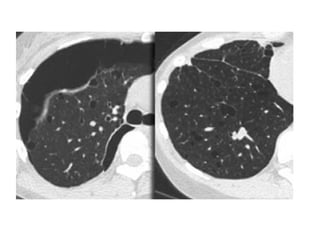

A, Unenhanced axial high-resolution CT through left mid (A) and lower (B) lung

show peripheral honeycombing, which is greatest in lower lobe,

accompanied by traction bronchiectasis and scattered peripheral reticular

opacities. Honeycombing is most prominent feature in this patient, typical for

idiopathic pulmonary fibrosis